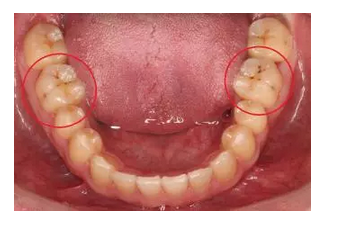

牙齒出現(xiàn)的齲壞,從外面看就表現(xiàn)為一個黑點,通常位于窩溝點隙(牙面上點狀或線狀凹陷)。齲齒的罪魁禍首是口腔中的某些細菌,但它們破壞牙齒也是需要時間的,從初期的變色到最終形成齲洞,通常需要1年半到2年。在此期間,我們多留心自己的牙齒,完全可能把齲壞扼殺在萌芽階段。如何才能及時發(fā)現(xiàn)這種隱匿的蛀牙呢?找位好牙醫(yī),半年檢查牙齒!

一旦確認牙齒上的小黑點是齲齒就應(yīng)該盡早修補,以阻止病變的發(fā)展。如果任由其繼續(xù)發(fā)展就會變成明顯的齲洞,這時患者會對冷熱酸甜等食物刺激敏感;當(dāng)損傷進一步到達牙髓(即老百姓說的“牙神經(jīng)”),就會疼痛難忍,嚴重影響日常生活。